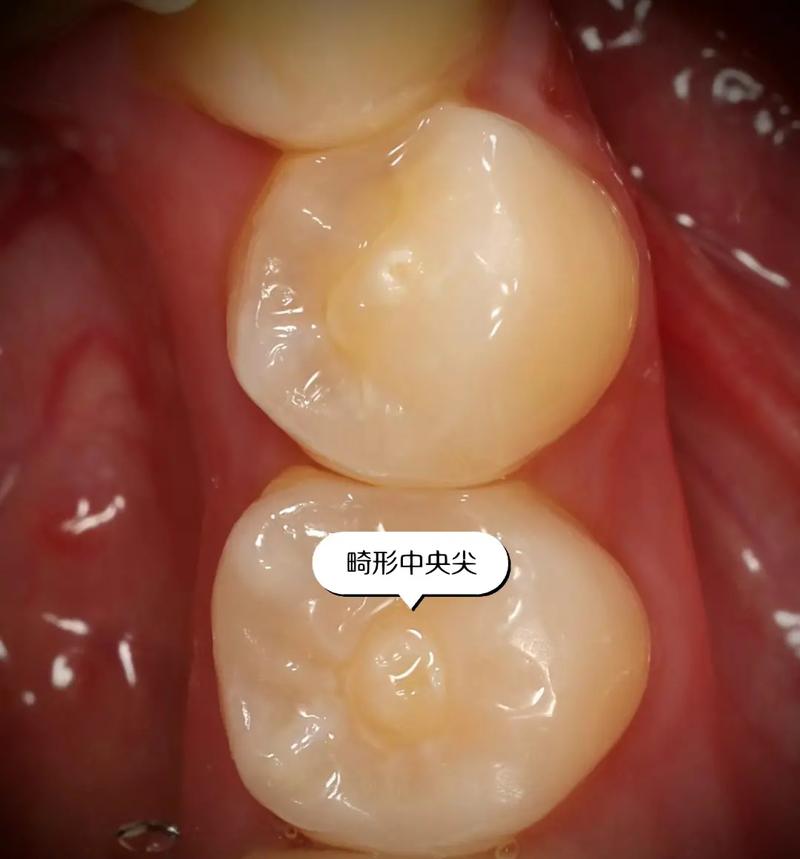

尖牙的結(jié)構(gòu)與功能尖牙,顧名思義,其尖銳的外形使其在咀嚼硬物時(shí)表現(xiàn)出色。其位于牙弓的特殊位置,能夠有效地撕裂食物,確保食物的適當(dāng)消化。尖牙的中間尖牙齒面,具備獨(dú)特的磨耗模式,這種磨耗不僅影響食物的處理方式,也對(duì)鄰近牙齒的排列和健康產(chǎn)生深遠(yuǎn)影響。

尖牙的健康直接影響整個(gè)口腔的生態(tài)系統(tǒng)。其表面的健康狀況可反映出個(gè)體的飲食習(xí)慣與口腔衛(wèi)生。若尖牙面出現(xiàn)齲齒或磨損,可能導(dǎo)致咀嚼功能下降,進(jìn)一步引發(fā)牙周病等其他口腔問(wèn)題。定期檢查與適當(dāng)?shù)目谇蛔o(hù)理至關(guān)重要,以維持尖牙的功能與美觀。